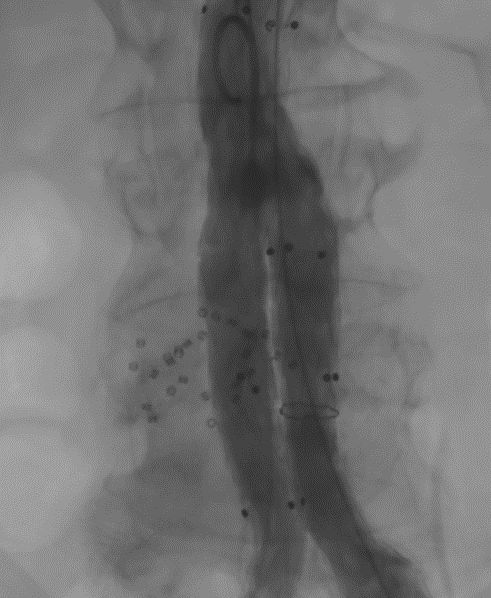

Aneuryzma aorty je život ohrozujúce ochorenie s vysokou úmrtnosťou. Dnes sme na našom Angiologickom oddelení, ako prví na východnom Slovensku, liečili aneuryzmu brušnej aorty pomocou bifurkačného stentgraftu v kombinácii s vypĺňaním vaku biopolymérnym vstrebateľným materiálom Impede. Na rozdiel od použitia klasickej endovaskulárnej liečby aneuryzmy aorty (EVAR), tento inovatívny výkon pomáha pacientom s EVAR predchádzať vzniku endoleakom, čím sa znižuje potreba ďalších reintervencií po endovaskulárnej liečbe. Týmto špecializovaným a náročným výkonom sme sa zároveň zaradili medzi popredné svetové pracoviská, kde sa tento výkon realizuje.